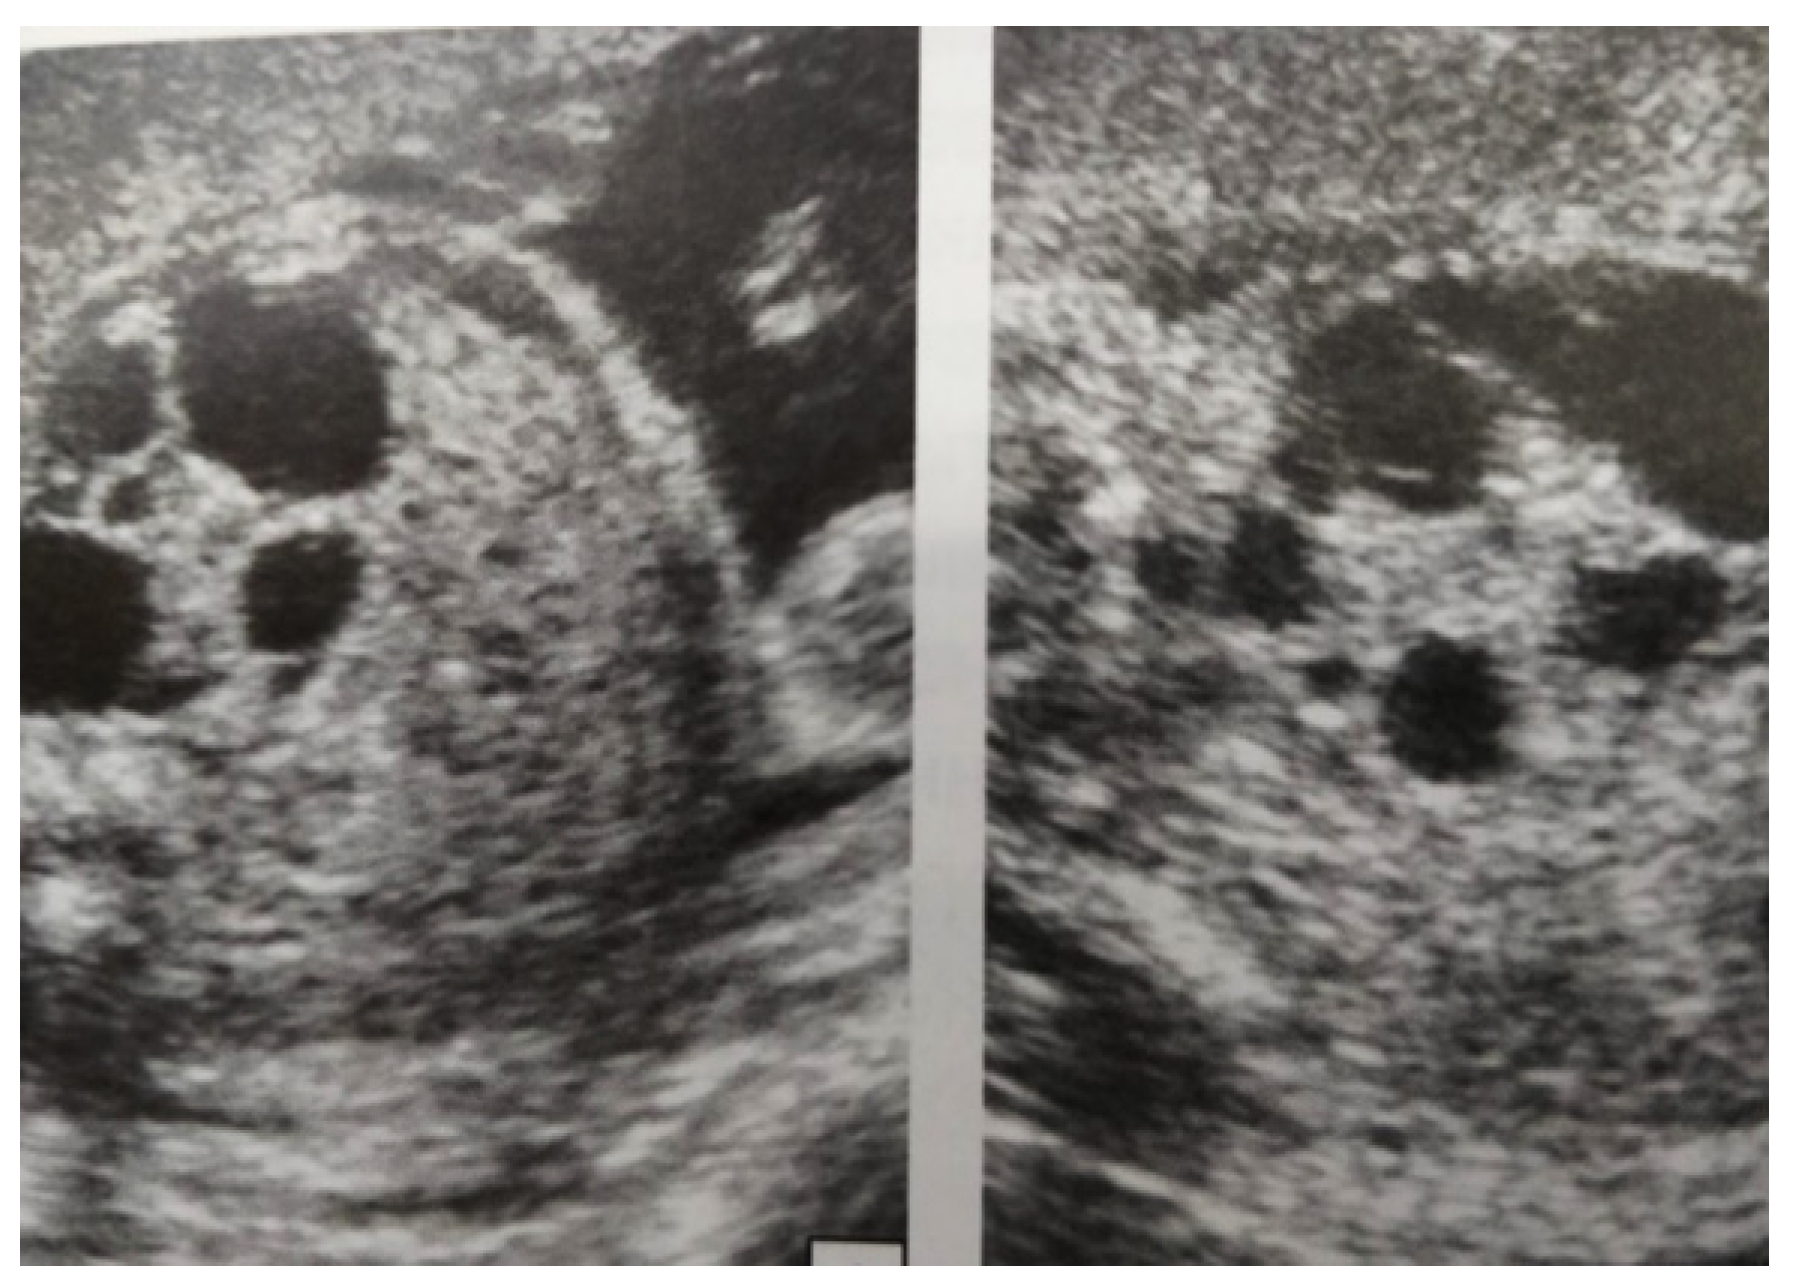

Our experience with congenital malformations of the urinary system refers to the following clinical case (Figure 2, Figure 3, Figure 4, Figure 5, Figure 6, Figure 7, Figure 8 and Figure 9). In the first case, during pregnancy, the 21-week ultrasound determined bilateral renal pyelectasia. The fetus had hydronephrosis on the right; at 31 weeks, it had bilateral hydrocalconephrosis; and at 32 weeks, bilateral pyelectasia. It suffered premature birth at 36 weeks, with complicated anomalies of the forces of contraction, prolonged birth, and birth weight of 2200 g. Postnatal ultrasonography was supplemented by intravenous urography, and bilateral hydronephrosis was determined. Hydrocalconephrosis on the left was discovered. The complete diagnosis was established: congenital renal malformation; bilateral pyelectasia; bilateral hydronephrosis; hydrocalconephrosis on the left; and severe reduced glomerular filtration rate (GFR), GFR > 2SD below mean.

Figure 4. Ultrasound at 31st week of gestation. Bilateral hydrocalconephrosis.

Figure 5. Ultrasound at 32 weeks of gestation. Bilateral pyelectasis.